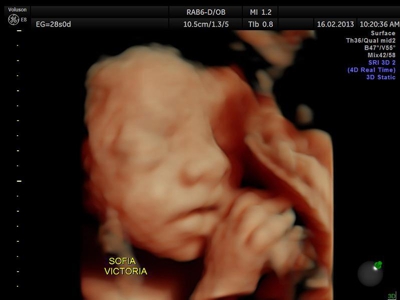

La ecografía 4D HD/5D consiste en la adquisición y presentación continúa de volúmenes. La denominación de la técnica obedece a que hay cuatro dimensiones involucradas: ancho, largo, profundidad y tiempo.

Si bien la Ecografía 4D HD/5D puede realizarse en cualquier etapa del embarazo, recomendamos realizarla entre las semanas 24 a 32 de gestación ya que se pueden observar rasgos bien definidos en el bebe.

Fotografías de ecografías 4D HD/5D

Haga click sobre las imágenes para ampliar